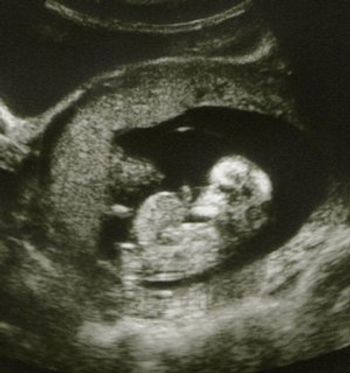

An approx. 12 week fetus, first ultrasound of this pregnancy.